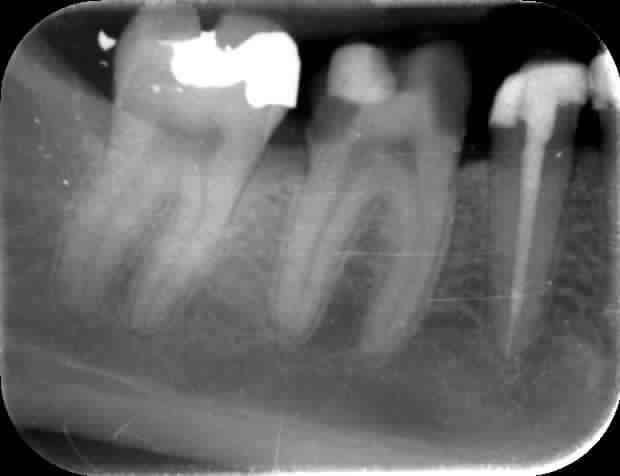

Je joins une radio sur laquelle il me semblait que la pulpe était nickel. Ce que confirme d'ailleurs la sensibilité au froid lorsque j'ai fini ma taille mais qui a disparu à l'arrêt de l'agression mécanique

Onlay1 hbdcrn - Eugenol

En distal, on n'est quand même pas trop loin de la pulpe. Personnellement, j'aurais sans hésiter, proposé une ccm sur la dent vivante.